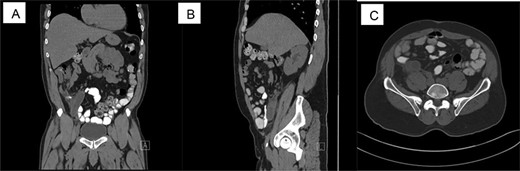

CT scan shows acute appendicitis. Dilated fluid-filled appendix measuring up to 2.4 cm in diameter × 8.3 cm in length with periappendiceal inflammation ((A) Coronal view, (B) sagittal view, (C) axillary view).

A 65-year-old male patient with a pertinent past medical history of hypertension, type 2 diabetes mellitus, alcohol and tobacco use presented with right-sided abdominal pain. The patient stated that the pain started 3 days prior, with a previous hospital visit the day before but the patient left against medical advice. The patient described the pain as sharp, intermittent, 8/10 and constant. He denied any fever, chills, nausea, vomiting, diarrhea, dysuria, any significant weight loss, changes in bowel habit or previous colonoscopy. His vital signs on presentation were temperature of 98.9°C, heart rate of 101 bpm, respiratory rate of 16 breaths/min, blood pressure of 117/68 mmHg and oxygen saturation rate of 95% on room air. On focused physical examination, the abdomen was tender to deep palpation in the right lower quadrant with a negative Rovsing’s sign, no rebound and no guarding, which correlates with a clinical diagnosis of acute appendicitis. Imaging showed a dilated fluid-filled appendix measuring up to 2.4 cm in diameter × 8.3 cm in length with periappendiceal inflammation as well as a trace left hydroureter and a non-obstructing right renal calculus. On admission, the patient had leukocytosis of 11.5 with a differential of 75.7% neutrophils and 14.5% lymphocytes. Patient was placed on intravenous antibiotics (Zosyn) and taken for laparoscopic appendectomy.